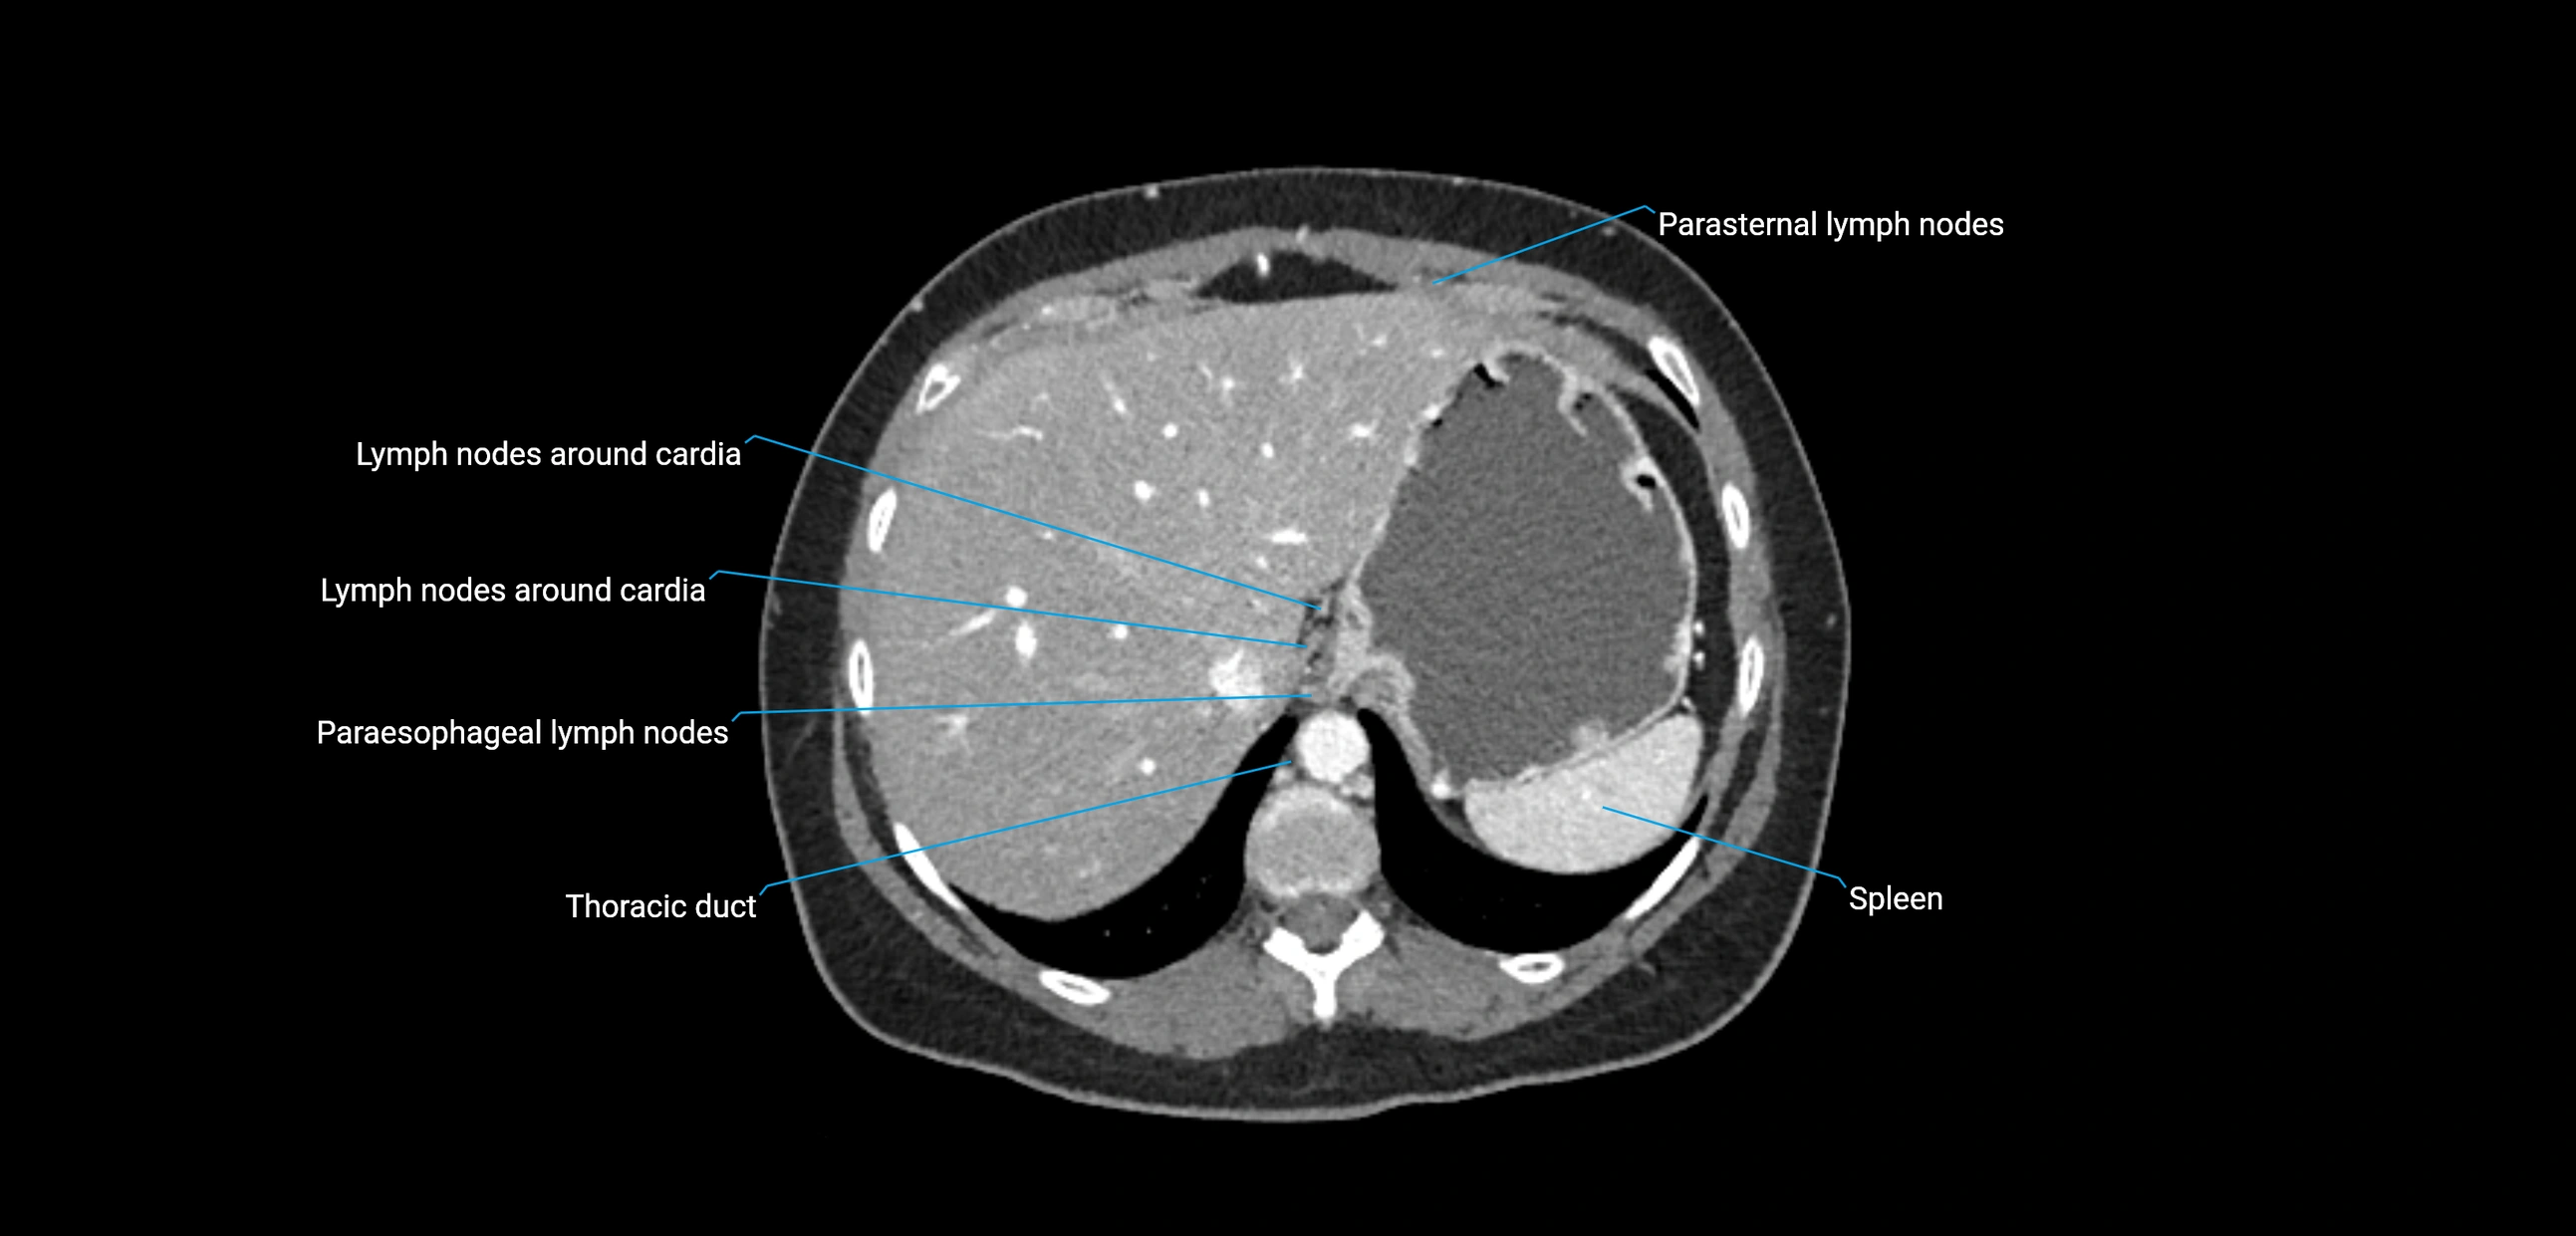

CT image

image